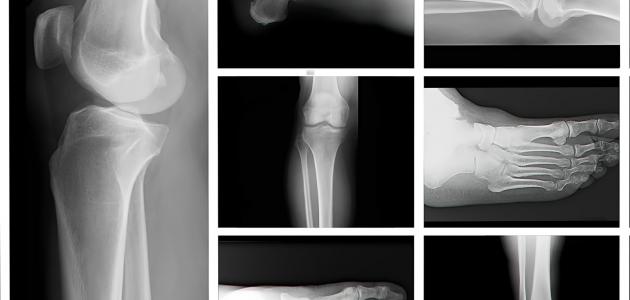

انواع الكسور

إن أنواع الكسور تتلخص في أربعة حالات :

1- كسر بسيط أو مغلق : وفي هذا النوع من الكسور يظل الجلد الخارجي سليما دون أن يتمزق أو يجرح كما لا توجد أي إصابات في الأغشيةالتي حول العظم.

2- الكسر المفتوح : وهذا الكسر يصاحبه جروح في الجلد الخارجي ، وفي بعض الحالات

وقد يخرج طرف العظم المكسور من فتحة الجرح المقابل للكسر.

3- الكسر المضاعف أو المركب : وفي هذا الكسر تصاحبه إصابات في الأعضاء الداخلية المجاورة له كالأوعية الدموية ، أو المخ أو الرئة أو الكبد ، حسب مكان العظم المكسور وقربه من العضو المتأذي.

4- كسر الغصن الآخر (الشعر) : وهي من أكثرالكسور التي تصيب الأطفال ، ويكسر فيها العظم من الداخل وتبقى الطبقة التي تغلقها سليمة (السمحاق الخارجي).